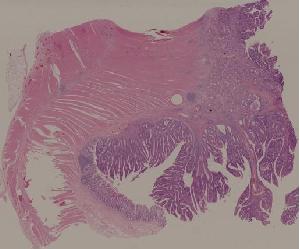

28.结肠腺瘤